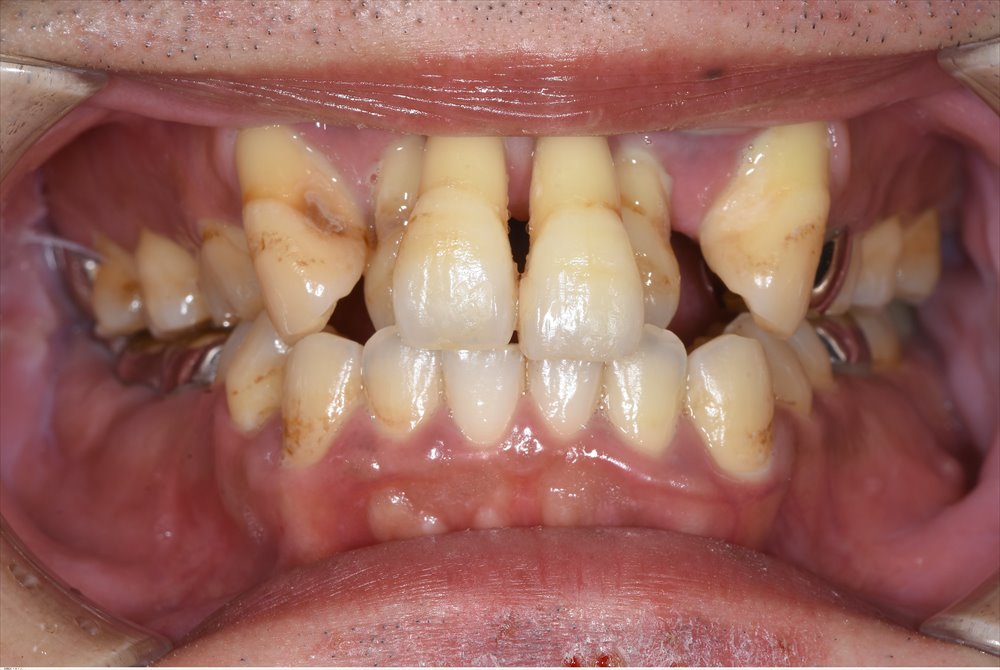

初診は2年前です。

全体的な重度歯周病でした。

前歯だけではなく奥歯も重度歯周病

歯周病専門医の腕の見せ所です。